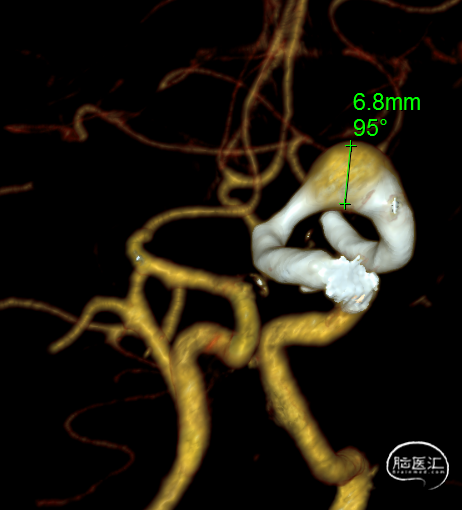

题目:左侧大脑中动脉M1段夹层动脉瘤FD植入术

Title:Flow Diverter (FD) implantation for a dissecting aneurysm at the M1 segment of the left middle cerebral artery

摘要:47岁中年女性,因头部外伤后发现颅内动脉瘤4个月入院。诊断:左侧大脑中动脉M1段夹层动脉瘤。经过术前充分抗血小板药物治疗后,首先球囊扩张夹层近端的狭窄,然后植入血流导向装置覆盖整个血管夹层,术中发现支架打开不良,给予支架内球囊扩张及微导丝按摩处理后最终支架完全打开,夹层段血管得到修复,围手术期未出现神经缺损,术后5个月随访,mRS评分为0分。

Abstract:A 47-year-old female was admitted for the treatment of an intracranial aneurysm found 4 months following a head trauma. The diagnosis confirmed a dissecting aneurysm at the M1 segment of the left middle cerebral artery. After preoperative antiplatelet therapy, a flow-diverting device was deployed following balloon angioplasty of the dissection's proximal stenosis. Intraoperative stent misdeployment was corrected with additional balloon dilation and micro-guide wire manipulation, leading to full stent expansion and vascular reconstruction. No neurological deficits occurred perioperatively. At the five-month follow-up, her modified Rankin Scale (mRS) score was 0, indicating a complete recovery.

诊断:左侧大脑中动脉M1夹层动脉瘤。

L ICA 3D

AN长径9.14mm

远端血管大脑中直径2.34mm、近端颈内末端4.25mm